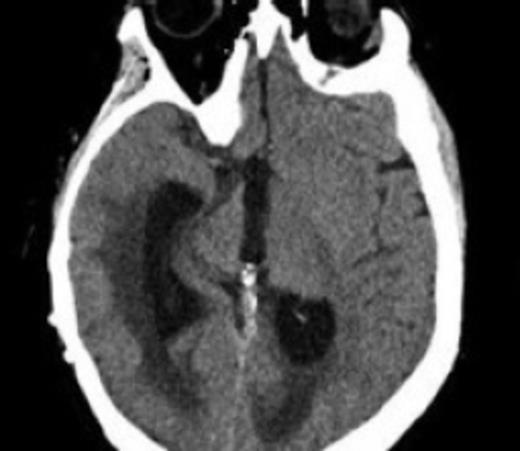

We report the case of a 34-year-old woman with a history of pilocytic astrocytoma resection and radiotherapy with ventriculoperitoneal shunt placement as a child who presented with altered mental status and nausea. She was found to have acute hydrocephalus without any pathology noted on MRI (Fig. 1). She was found to have a shunt fracture at the level of the neck and was taken to the operating room for shunt revision (Fig. 2). At this time, she had an entirely new shunt placed including a programmable valve with an anti siphon device. Post-operatively she did well and was discharged home.

CT scan showing acute enlargement of the ventricles post initial revision demonstrating shunt failure